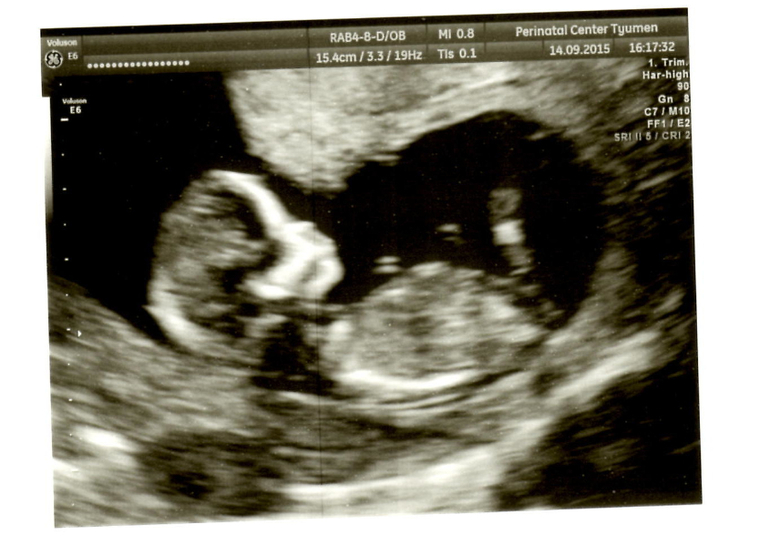

Вот и состоялась снова наша встреча с малышом)) Он так подрос за эти 2 недели.. срок еще на один день уменьшился.. должен был быть 12,6, а оказалось 12,5. Так бы и любовалась малышом хоть раз в неделю.. эх.. с малышом все хорошо.. 161 удар сердечка..он вообще похоже спал когда его смотрели.. потом когда пришел папа и нам сказали пол ребенка.. меня эмоции переполняли и он проснулся.. и мы увидели как он потягивается.. ооо.. это так мило =)) Сказали будет мальчик))) Значит внутри меня растет Савелька =)) забавно что когда я узнала о беременности сказала, что там мальчик.. так как никак не получалось зачать.. а когда мы наконец купили машину.. он зародился во мне.. Теперь папа начал мечтать какое царство игрушек у нас будет)) Я тоже рада.. всегда первым хотела мальчика.. старшим хочется брата, а младшенькой сестренку) А вот наши первые фото.. правда не такие они четкие как мне думалось будут..